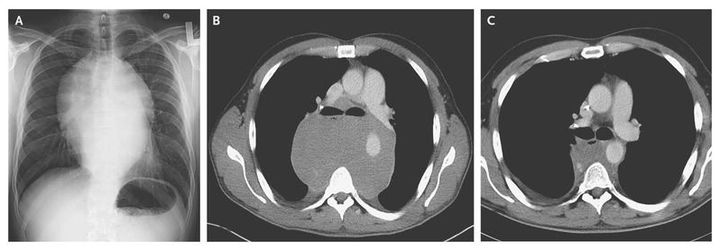

A 30-year-old man presented with chest pressure, shortness of breath, severe dyspnea on exertion, dysphagia, odynophagia, and a weight loss of 30 lb (14 kg) over a 2-month period. He had undergone orchiectomy 3 years earlier for stage 1 testicular seminoma but had been lost to follow-up. Cardiac examination revealed normal sinus rhythm without murmurs or gallops, and the lungs were clear on auscultation. Radiography (Panel A) and computed tomography (CT) (Panel B) of the chest revealed a large, posterior mediastinal mass. On CT, the mass measured 19 cm by 15 cm by 8 cm, displaced adjacent structures, and circumscribed the descending thoracic aorta. A CT scan of the abdomen was unremarkable. Laboratory evaluation revealed a human chorionic gonadotropin level of 4 mIU per milliliter (normal value, <3), a lactate dehydrogenase level of 1400 U per liter (normal range, 140 to 270), and a normal alpha-fetoprotein level. Findings on biopsy were consistent with seminoma. The patient received three cycles of chemotherapy with bleomycin, etoposide, and cisplatin, with substantial improvement in his symptoms. A follow-up CT scan 3 months later (Panel C) revealed a marked decrease in the size of the mass. After 10 months of follow-up, the patient is asymptomatic and is doing well, with continued follow-up every 4 months.